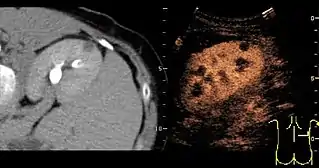

Unspecific cortical lesion on CT scan is confirmed cystic and benign with contrast-enhanced renal ultrasonography.

Most renal cell carcinomas are now found incidentally.[19] Tumors less than 3 cm in diameter less frequently have aggressive histology.[20]

A CT scan is the first choice modality for workup of solid masses in the kidneys. Nevertheless, hemorrhagic cysts can resemble renal cell carcinomas on CT, but they are easily distinguished with Doppler ultrasonography (Doppler US). In renal cell carcinomas, Doppler US often shows vessels with high velocities caused by neovascularization and arteriovenous shunting. Some renal cell carcinomas are hypovascular and not distinguishable with Doppler US. Therefore, renal tumors without a Doppler signal, which are not obvious simple cysts on US and CT, should be further investigated with contrast-enhanced ultrasound, as this is more sensitive than both Doppler US and CT for the detection of hypovascular tumors.[21]